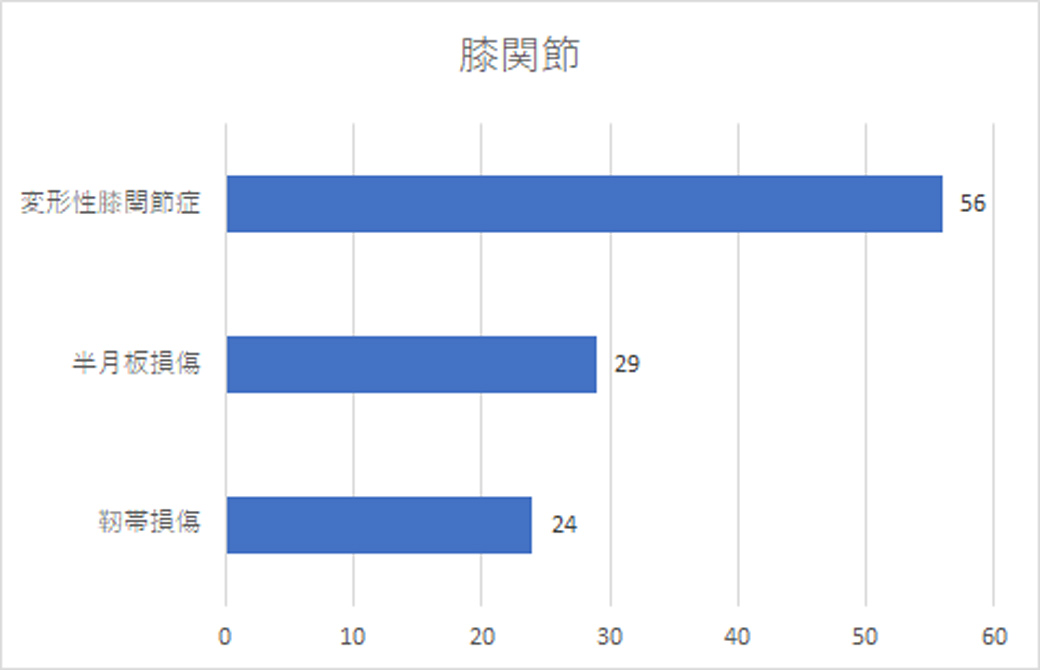

人体で最も大きな関節。膝関節の1位は変形性膝関節症

大腿骨と脛骨、そして膝蓋骨で構成されている、膝関節。この関節は、蝶番関節といって、関節がちょうどドアの蝶番(ちょうつがい)のような仕組みになっていて、一方向にだけ曲げ伸ばしができるようにその運動が制限されています。

変形性膝関節症は、この膝関節の軟骨がすり減り歩行時などに痛みが出てくる疾患のこと。正座が出来なかったり、和式のトイレが使えなかったりと日常生活に支障が出てきます。

また、2位に来ている「半月板損傷」。これは、膝関節内にある半月板に亀裂が生じたり、欠けたりした状態を云います。スポーツによる怪我の他、加齢によって発症することもあります。症状としては、膝の痛みや関節の違和感、引っかかり感、異常音などがあります。

膝関節は、体重を支えている関節の一つであるため、平坦な道を歩くだけで体重の2~3倍の負荷がかかっています。できるだけ大切にしたい関節ですね。